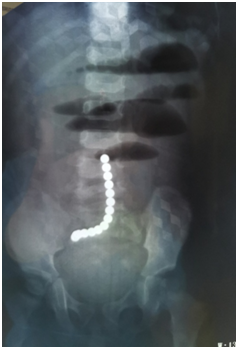

5月19日,1岁2个月小馨馨被爸爸妈妈抱着,一路从当地医院紧急转到同济医院小儿外科,检查发现小馨馨易发生肠梗阻、弥漫性腹膜炎,拍片显示腹腔内有一串长长的链珠,证实又是一例误吞磁珠病例。医生立即实施了急诊手术才挽救了小馨馨的生命。

当幼儿分次吞入的磁球随小肠蠕动向下运动,由于肠管柔软、狭长和弯曲,当不同位置的磁球运行到邻近的肠曲部位时,强大的磁力相互吸引,立刻夹挤双层肠管,此时磁球不能再运动,压住的肠管逐渐缺血、坏死,最后穿孔。如果肠管其他部位还有磁珠,就会依次再发生吸引夹挤肠管,最后磁珠形成链珠状,夹挤的肠管相互折叠,形成肠梗阻。由于每次夹挤的都是双层肠管,所以肠穿孔一般都是偶数。小馨馨的腹部平片显示有14颗磁珠,手术证实小肠共有6处穿孔,说明这十四粒磁珠聚集了四处,夹住三处共六段肠管。